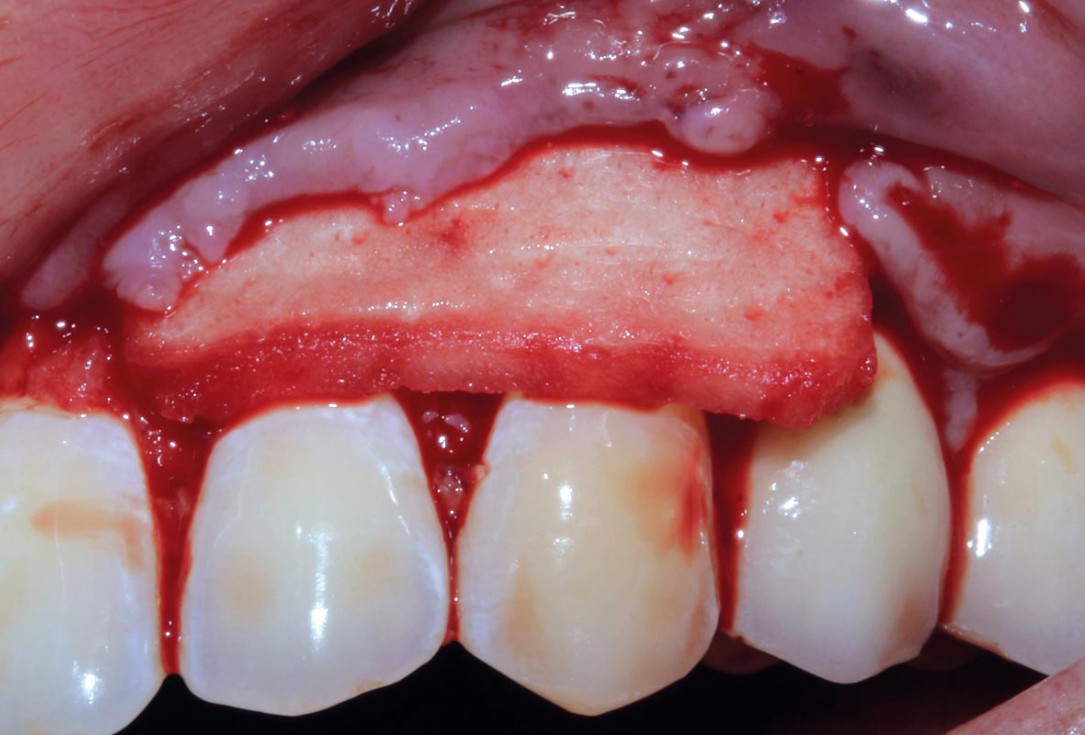

04/10 - mucoderm® soft tissue graft hydrated in bloodTreatment of single gingival recession with mucoderm® – Dr. A. Hamdy